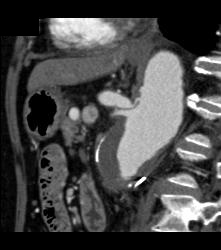

Intraductal Papillary Mucinous Neoplasm (IPMN) With Normal Splenic Artery and Vein